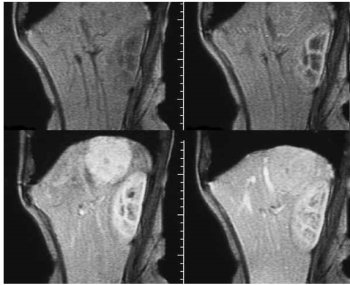

- IV.3.8. Kontrasztanyagok